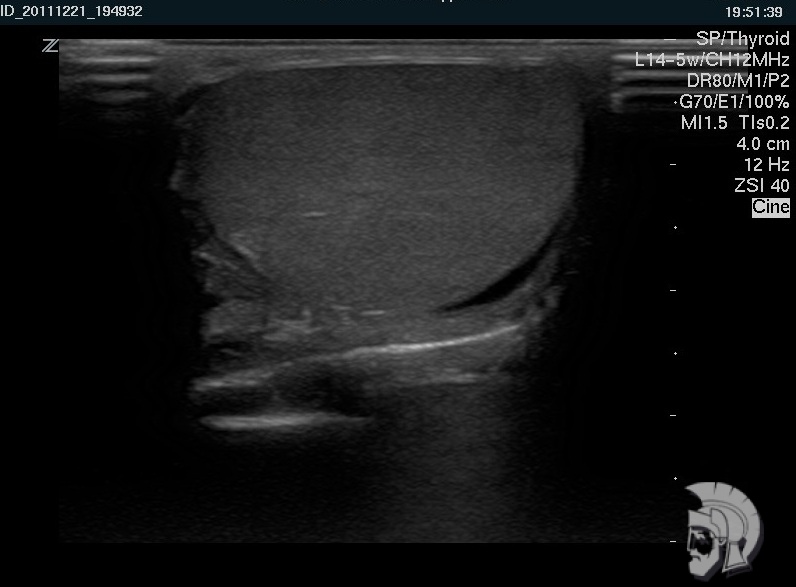

Резкая боль в паху заставила обратиться к врачу. После диагностики на специальном аппарате УЗИ было назначено скорое лечение. Спасибо за быструю диагностику и лечение! Очень тактичный и профессиональны й персонал! С ув. Михаил Васильевич, г.Пятигорск.